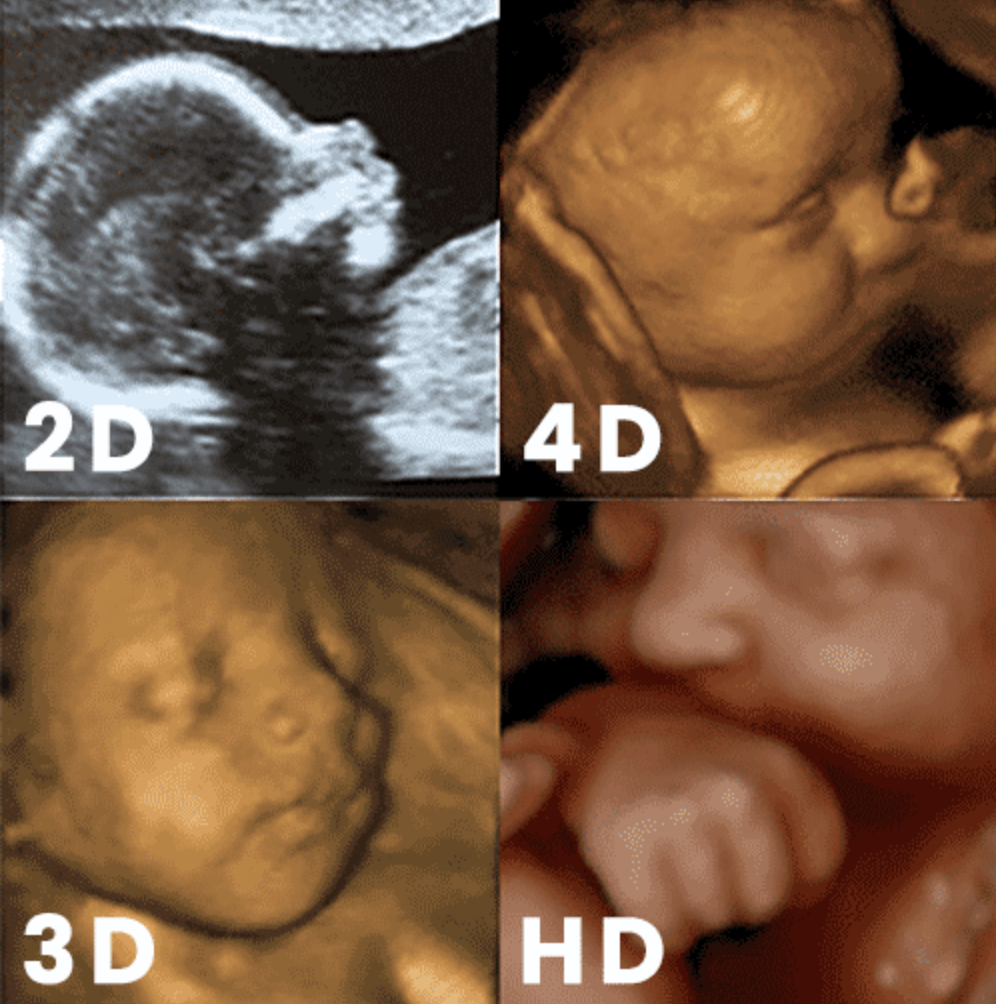

What is the difference between 2d, 3D, 4d & 5d

As the most common form of ultrasound, a 2D ultrasound creates a black and white image that shows the skeletal structure of the baby and makes the internal organs visible. The 2D ultrasound is most commonly used to diagnosis the health of the baby. As the name implies, all 2D images are flat and have no depth to them.

Much like 2D ultrasounds, a 3D ultrasound uses soundwaves to develop an image of the baby inside of your womb. However, unlike the flat image given by a 2D ultrasound, a 3D ultrasound creates the appearance of a three-dimensional image of the baby. This allows the expecting parents to see their baby’s face, rather than just the outline of the face.

4D ultrasounds also create a three-dimensional image and provide an even clear image of the baby. The 4D ultrasound is created while capturing a video of your baby. We then scroll through the video and save still images. With 4D ultrasound imaging, you could potentially see your baby smile or yawn in the womb because it compiles hundreds of images into a moving video.

As the most recent advancement in ultrasound technology, HD and HD Live (also called 5D Ultrasound ) ultrasounds allow us to capture even clearer, sharper images. These images are more defined and have better resolution.